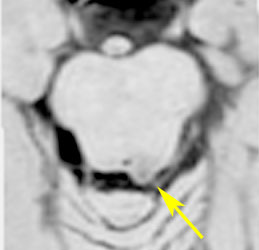

上段のガドリニウム増強MRIでは松果体腫瘍に見えやや境界が不明瞭なので,年齢からはPPTIDが疑われます。しかし,CISSの画像で,中脳上丘との境界がなく中脳腫大があるようにみえ,テクタールグリオーマを疑って経過観察しました。腫瘍がゆっくり増大したので摘出したところPPTIDという診断がつきました。